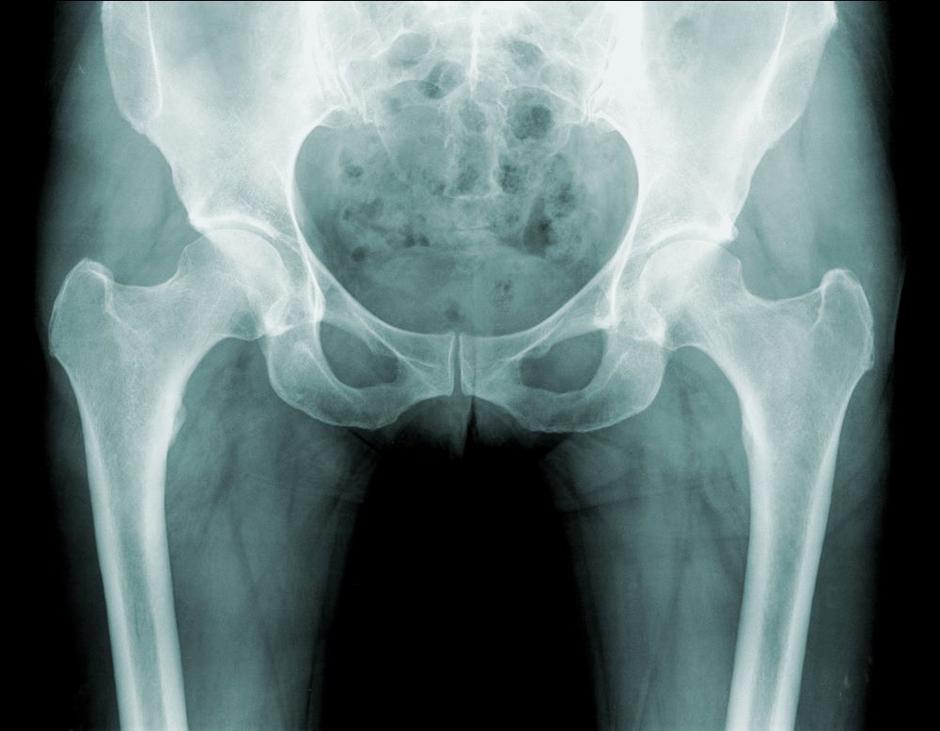

• Artroza kolka (degenerativna bolezen sklepov): Zmanjšanje bolečin in izboljšanje gibljivosti sklepa.

• Femoroacetabularna utesnitev (FAI): Zdravljenje omejene gibljivosti in bolečine, ki nastanejo zaradi nepravilne oblike kosti kolčnega sklepa.

• Displazija kolka: Rehabilitacija za posameznike z nepravilnim razvojem kolčnega sklepa, ki lahko vodi do bolečin in nestabilnosti.